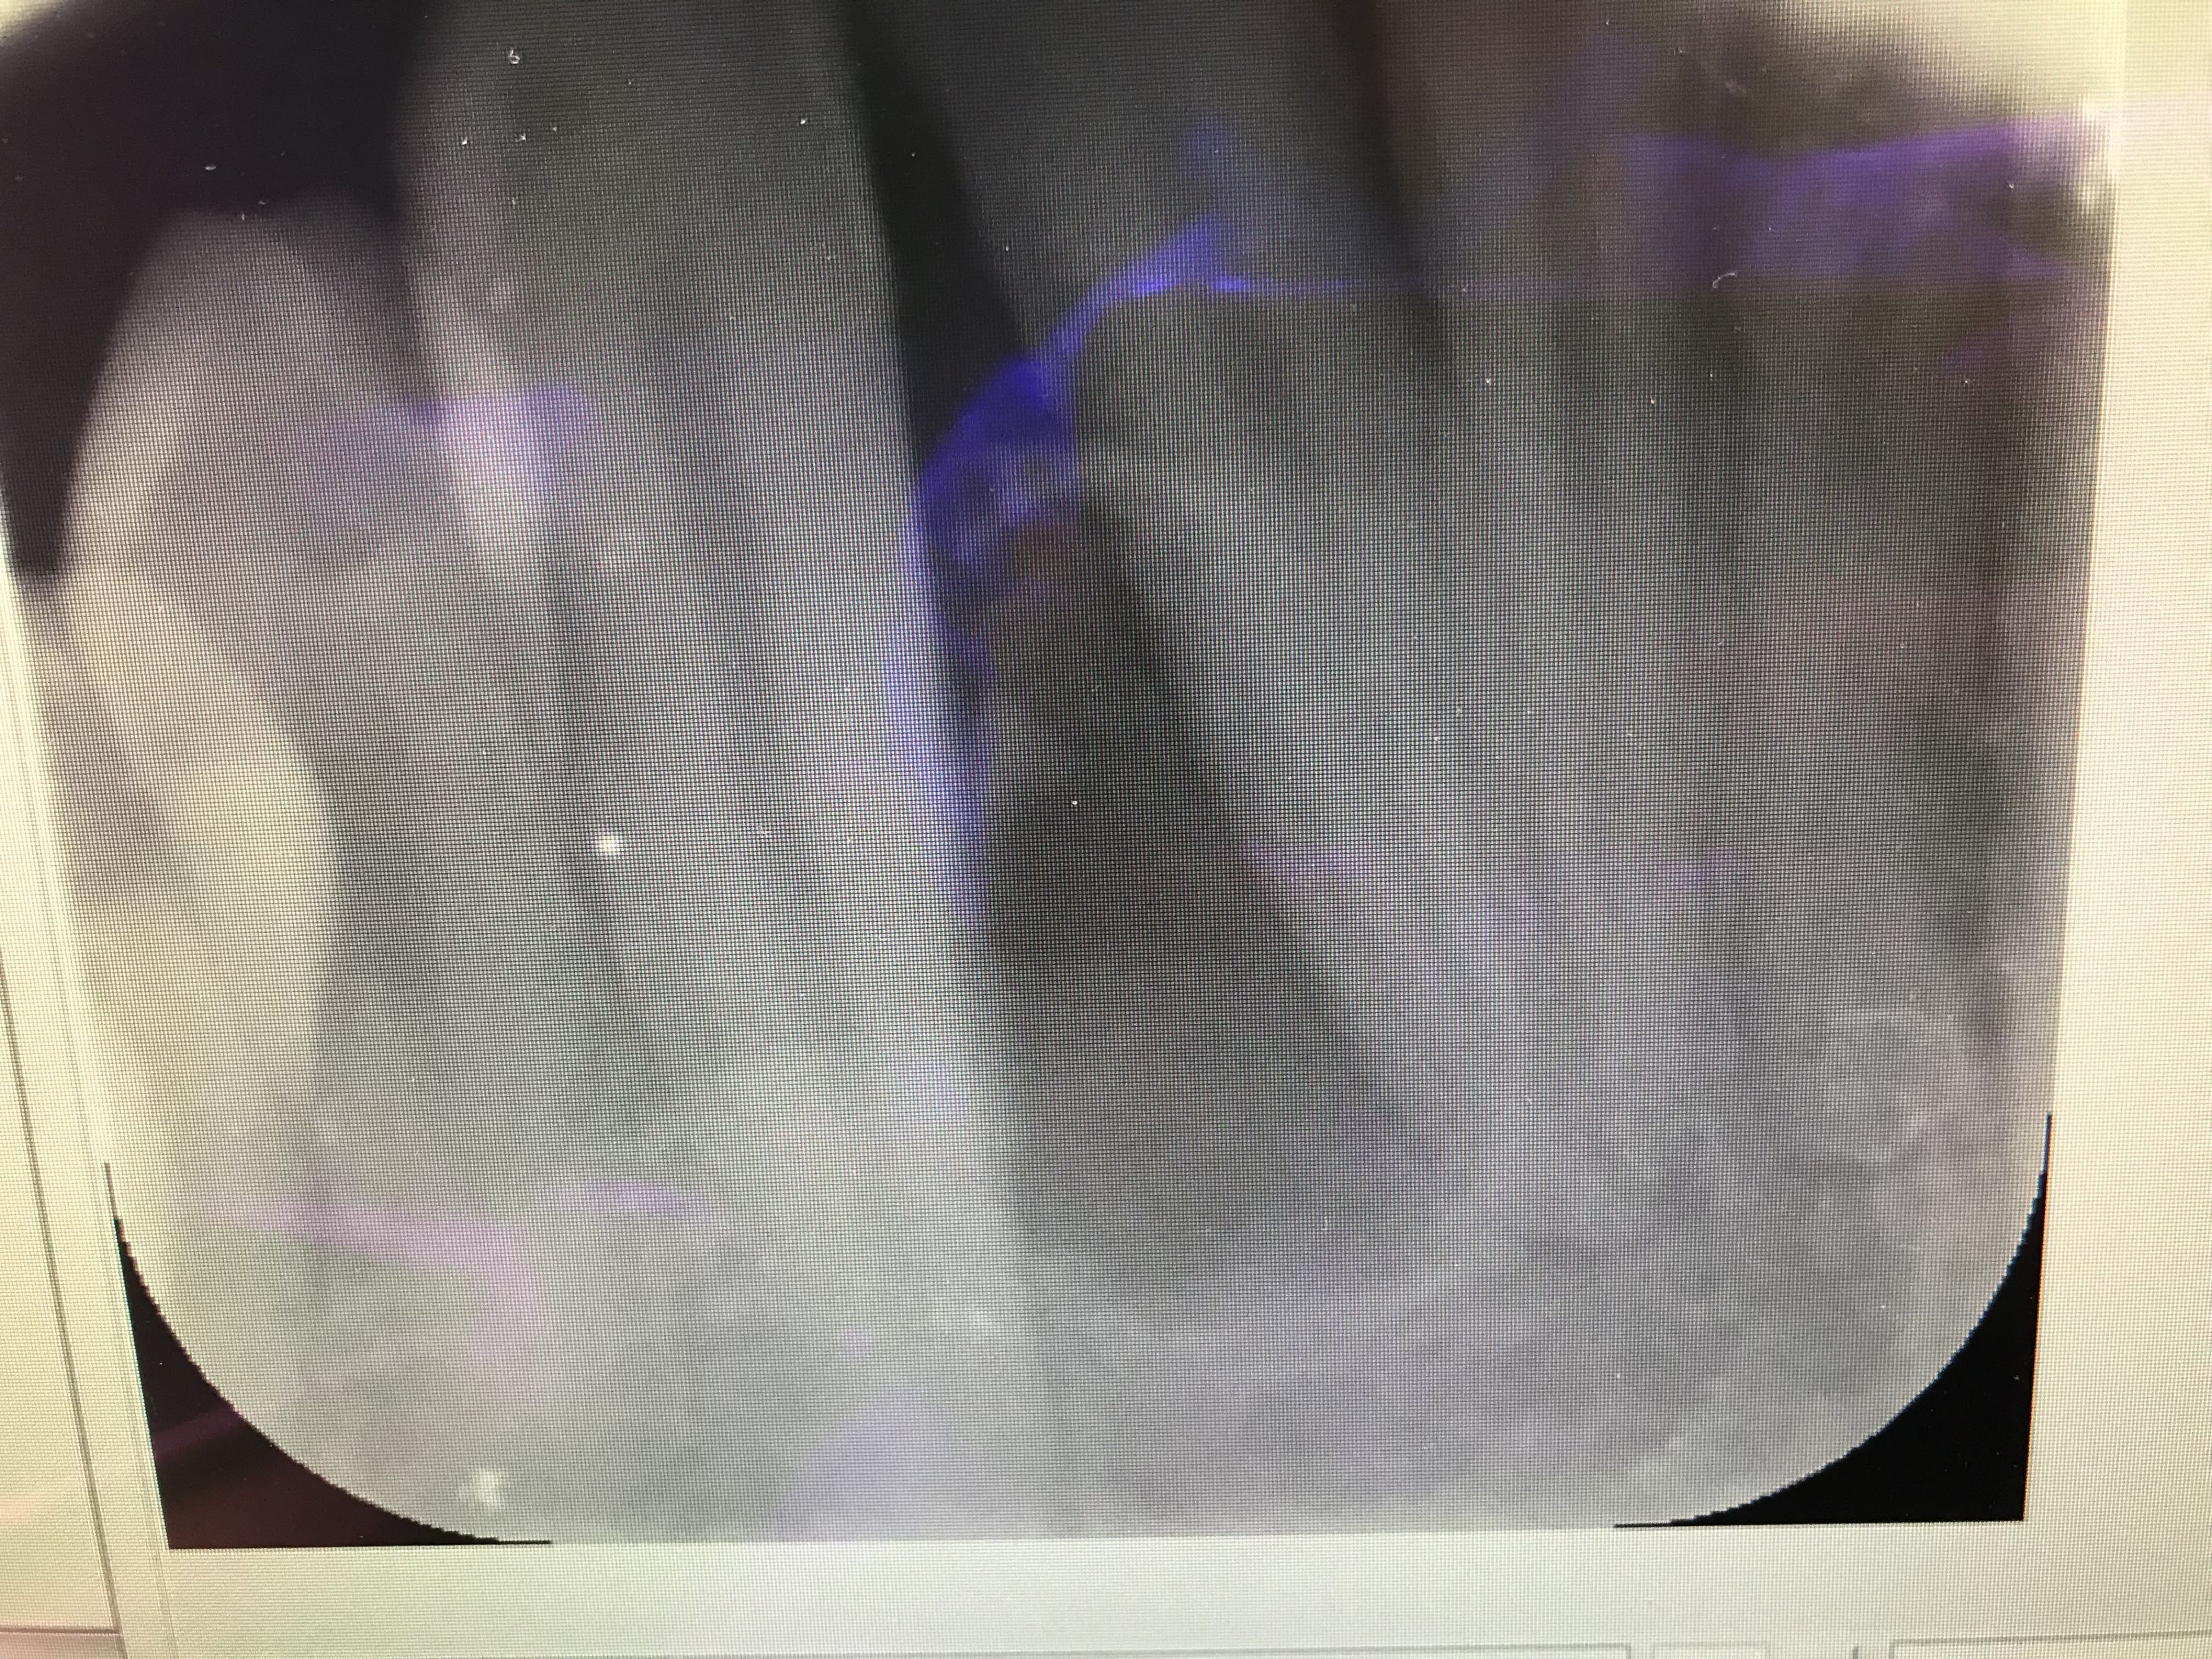

Un gros kyste entre 43 et 42?

Une dent surnuméraire?

C’est pgc qui a trouvé. T’as gagné une PPA à selles disjointes comme récompense ;))

Pour la petite histoire, il est venu au cabinet en m’expliquant qu’il avait fait une crise d’ épilepsie dans sa piscine et que depuis son incisive avait bougé. Il était persuadé que c’etait suite à un choc dans sa piscine .

Kyste parodontal latéral

D’ailleurs dans cet article ils racontent que ça a une croissance très lente. C’est faux il y a 3 mois il n’avait Absolument rien .... à croire que ça croît rapidement

Tu n'avais pas pris de radio il y a 3 mois. L'effet et la cause :-))) Un kyste latéro radiculaire ne met pas trois mois pour atteindre cette taille!

Je suis d’ accord sauf que sa dent était parfaitement droite il y a 3 mois. Ça prouve bien que ça évolue rapidement

Le kyste était peut être là il y a 3 mois . C’est certainement le cas .... sauf que il y a 3 mois les dents étaient alignées. Ce qui prouve que le kyste grossit rapidement